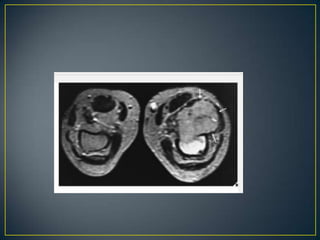

• MRI offers distinct advantages over CT.

• It has a few disadvantages as well.

• In the evaluation of intraosseous and extraosseous

extensions of a tumor, MRI is crucial because it can

determine with high accuracy the presence or absence of

soft-tissue invasion by a tumor .

• Assist in differentiation of intraarticular tumor extension

from joint effusion.

• Cant assess ossification and calcification.